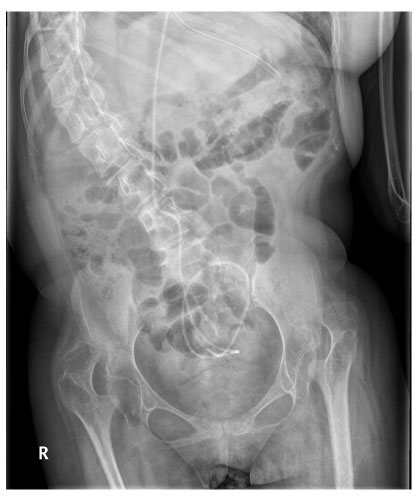

Fig. 2

Upper GI series at 14th day of surgery shows poor peristaltic activity of the stomach and delayed passage of barium through the pylorus. B. Upper GI series at 26th day of surgery reveals propulsive peristaltic activity of the antrum with prompt passage of barium through the pylorus to the duodenum immediately on injection of erythromycin.

Fig. 2 Upper GI series at 14th day of surgery shows poor peristaltic activity of the stomach and delayed passage of barium through the pylorus. B. Upper GI series at 26th day of surgery reveals propulsive peristaltic activity of the antrum with prompt passage of barium through the pylorus to the duodenum immediately on injection of erythromycin.